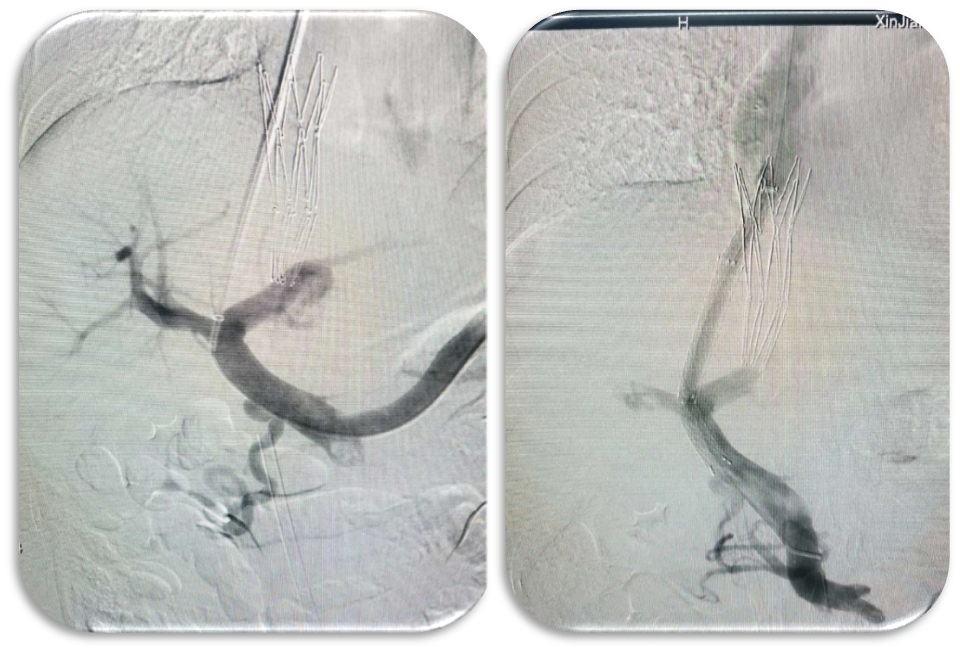

急诊 TIPS 应用

对于内镜反复止血失败的急性上消化道大出血患者,TIPS 可作为救命手段。我们曾接诊术中持续呕血的危重患者,通过急诊 TIPS 成功止血。

急性上消化道大出血急诊TIPS

多次内镜止血无效,急诊DIPS